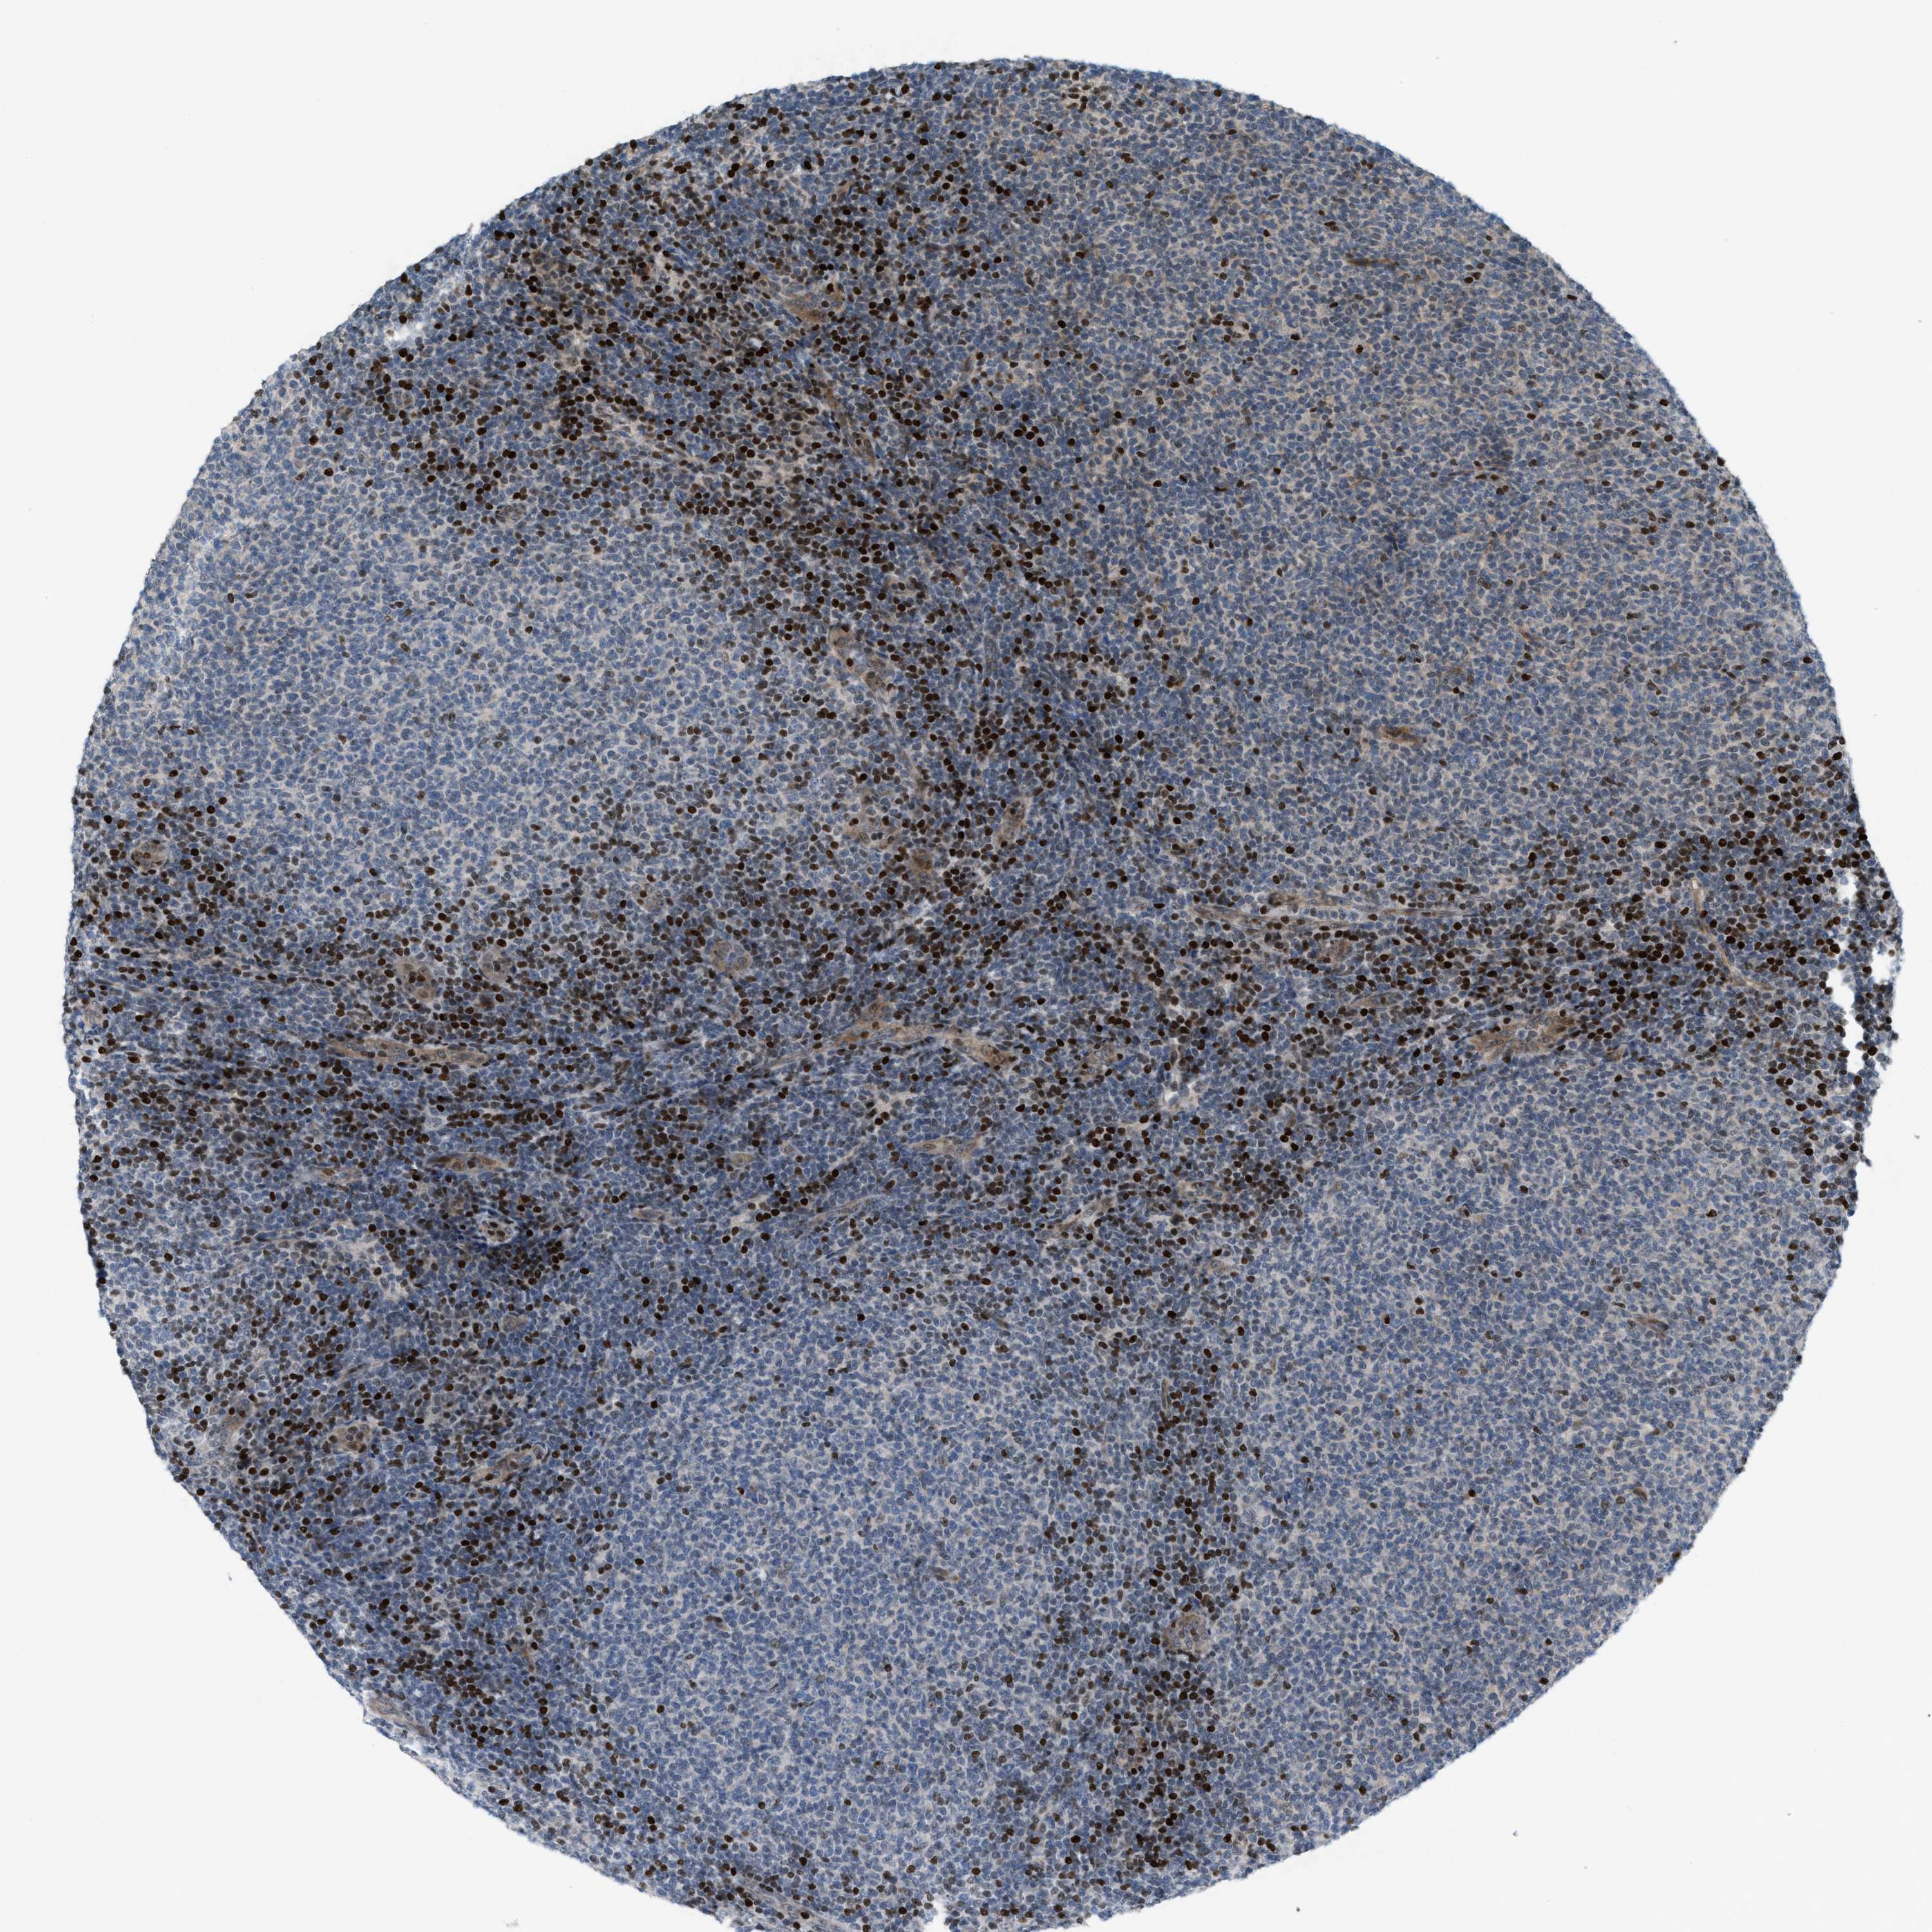

LYMPHOMA - Protein expressioni

A mouse-over function shows sample information and annotation data. Click on an image to view it in a full screen mode. Samples can be filtered based on level of antibody staining by selecting one or several of the following categories: high, medium, low and not detected. The assay and annotation is described here.

Antibody stainingi

Antibody staining in the annotated cell types in the current human tissue is reported as not detected, low, medium, or high, based on conventional immunohistochemistry profiling in selected tissues. This score is based on the combination of the staining intensity and fraction of stained cells.

Each image is clickable and will lead to virtual microscopy that enables deeper exploration of all samples and also displays staining intensity scores, fraction scores and subcellular localization as well as patient and tissue information for each sample.

Antibody HPA021309

Antibody HPA022255

Staining

High

Medium

Low

Not detected

Intensity

Strong

Moderate

Weak

Negative

Quantity

>75%

75%-25%

<25%

None

Location

Nuclear

Cytoplasmic/membranous

Cytoplasmic/membranous,nuclear

Hodgkin's disease, NOS

Malignant lymphoma, non-Hodgkin's type, High grade

Malignant lymphoma, non-Hodgkin's type, Low grade